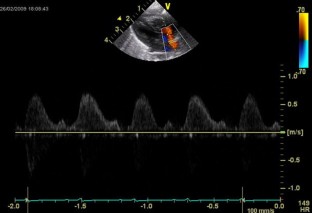

Fig. 1

Fig. 2